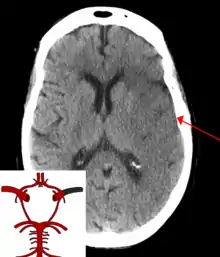

![]() | |

| CT scan of the brain showing a prior right-sided ischemic stroke from blockage of an artery. Changes on a CT may not be visible early on.[1] | |